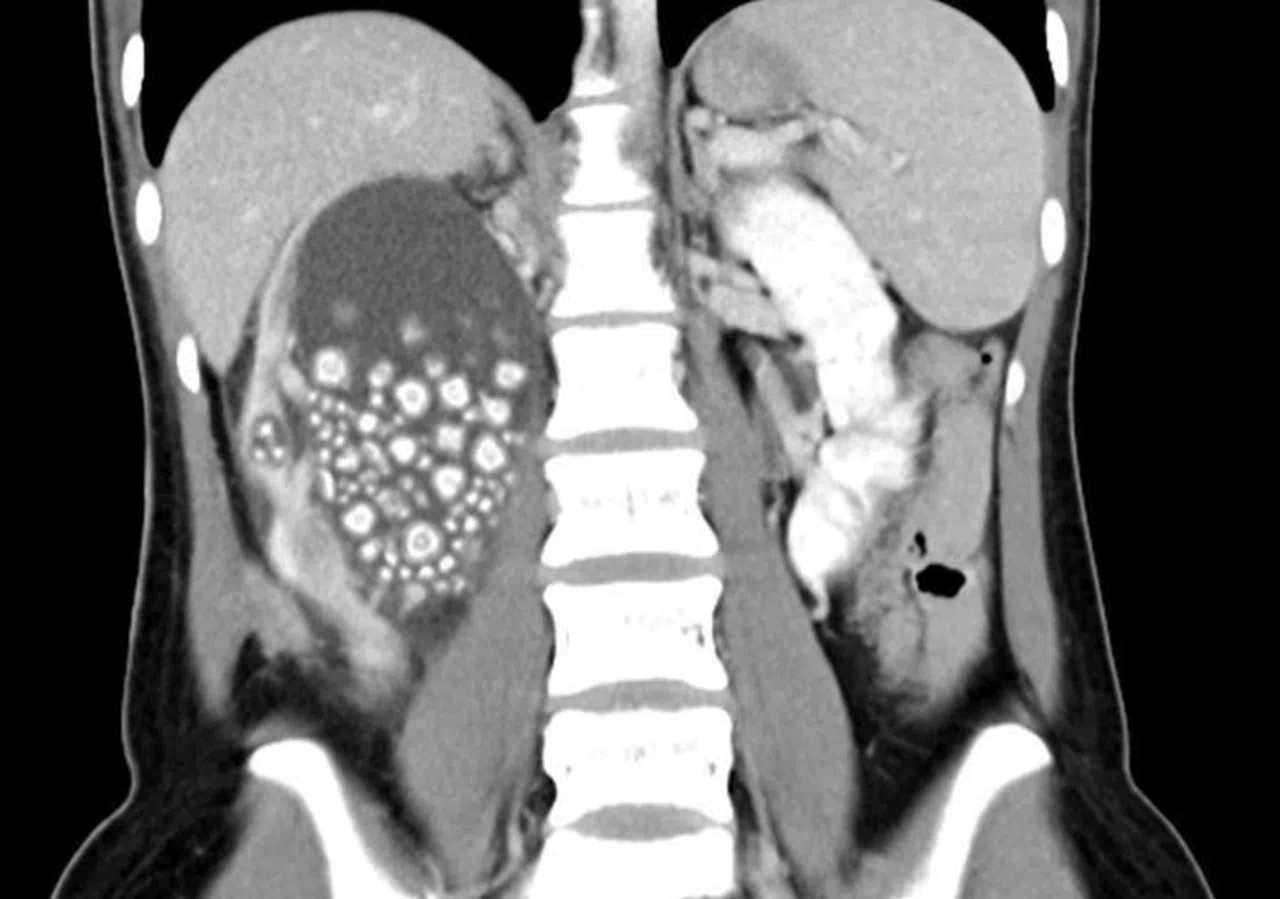

Tayvan’ın güneyinde yer alan Tainan şehrinde 20 yaşındaki Xiao Yu adlı biri sırt ağrısı şikayetiyle Chi Mei Hastanesi'ne başvurdu. Tetkiklerin sonucunda böbreklerinde çok sayıda böbrek taşı tespit edilen Yu acil ameliyata alındı. Başarılı geçen ameliyatın ardından Xiao Yu’nun böbreklerinden 0.5-2 cm boyutlarında 300’den fazla böbrek taşı çıkarıldı.